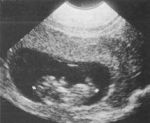

Una piccola pallina

si muove gesticolando

in calde acque,

si nutre

e cerca di assaporare

caldo amore.

E' al sicuro, al riparo

da onde assassine.

Intorno la vita scorre

scandendo attimi

di speranza.

Annaspa

quella piccola pallina,

cerca... leggi...